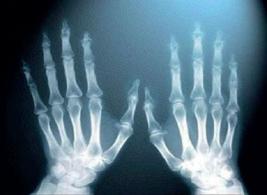

Кістки скелета людини відрізняються між собою за формою, розмірами, будовою, хімічним складом тощо. Навіть одні й ті самі кістки у скелетах різних людей можуть відрізнятися (наприклад, тазові кістки чоловіка і жінки різного розміру). Змінюються кістки і з віком людини. У молодому віці вони містять значно більше осеїну, а в людей похилого віку в кістках уже більше неорганічних речовин.

Розрізняють кістки парні (наприклад, ключиці) й непарні (наприклад, під’язикова кістка). Кістки класифікують на трубчасті, губчасті, плоскі, змішані та повітроносні.

Трубчасті кістки беруть участь у переміщенні тіла людини. Тому в них видовжене тіло, міцні головки, наявна порожнина, заповнена жовтим кістковим мозком. Довгими трубчастими є плечова, стегнова, а короткими трубчастими — фаланги пальців, кістки п’ястка. Губчасті кістки побудовані переважно з губчастої речовини і тонкого шару компактної речовини. Розрізняють довгі губчасті (ребра, грудина) і короткі губчасті (кістки п’ястка). Плоскі кістки побудовані з губчастої речовини з червоним кістковим мозком, яка зверху і знизу вкрита тонкими пластинками компактної (лопатка, скроневі, тазові). Така будова сприяє виконанню захисної функції. Змішані кістки можуть виконувати різні функції, тому складаються з декількох частин, що мають різну будову, форму і походження (хребці, нижня щелепа). Повітроносні кістки мають повітряні порожнини, вистелені слизовою оболонкою, і упродовж життя збільшуються (лобова, верхньощелепні). Ці кістки виконують захисну функцію, пристосовані для вентиляції повітря.

опорно-руховій системі людини?

Поняття «гіпокінезія» та «гіподинамія» мають різне значення, хоча вживаються як синоніми. Гіпокінезія (грец. «гіпо» — під і «кінезіс» — рух) — це обмеження рухового навантаження, що зумовлено способом життя, особливістю професійної діяльності, ліжковим режимом у період захворювання тощо. У низці випадків гіпокінезія супроводжується гіподинамією (грец. «динаміс» — сила), тобто зменшенням м’язових зусиль, які витрачаються на втримання пози, переміщення тіла в просторі, фізичну працю. Установлено, що основними гіподинамічними змінами в скелеті, які спостерігаються під час тривалої гіпокінезії, є зменшення кісткової маси, зниження мінеральної щільності кісткової тканини; водночас спостерігається функціональна атрофія скелетних м’язів, затримка росту кісток та ін. Найбільші зміни виявлені в кістках, які несуть максимальне опорне навантаження (стегнові кістки, кістки тазу та хребці).